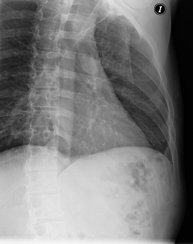

- Chest X-ray

This technique uses X-ray rendered imaging for examining the thoracic cavity (heart, lungs, costal arches, clavicles, etc.).

- Thoracic spine X-ray

This technique uses X-ray rendered imaging for examining the thoracic spine. Indicated for: trauma, pain, scoliosis.